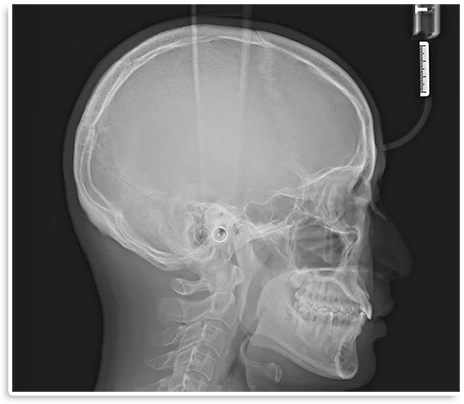

当院では、最新型のiTero Lumina による高精度な口腔内スキャニン グと、セファログラム(頭部X線 規格写真)などの検査データを組 み合わせて診断を行っています。

歯並びだけでなく、骨格バランス や横顔のラインまで多角的に分析 することで、従来の検査よりも精 密で総合的な治療計画の立案を可 能にしています。

頭部・顎骨の評価

• 緻密な

治療計画の

立案

• 頭部・顎骨

の評価

矯正治療に必要なセファログラムを併用することで、頭部全体の骨格バランスや将来的な変化まで考慮した分析が可能になります。その結果、より精度の高い治療計画を立てることができ、仕上がりの安定性にもつながります。